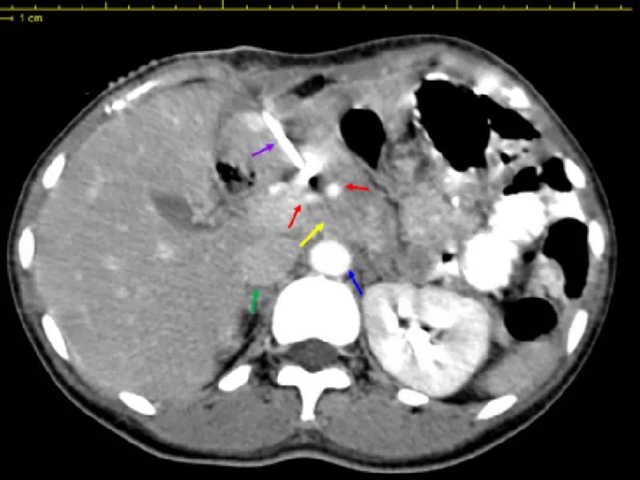

治疗中影像学显示

(黄色箭头为转移淋巴结,红色箭头为肿瘤前方小动脉,绿色箭头为下腔静脉,蓝色箭头为腹主动脉,紫色箭头为插植针)